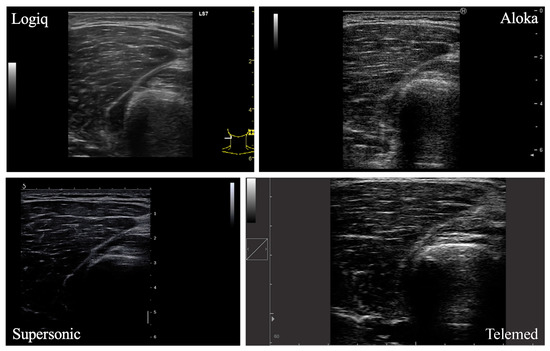

A total of four lower limb muscles were investigated in this study (VM, VL, GM, SOL; Figure 1). In each participant, the right leg was assessed by the same experimenter in a resting, supine position on an examination table. Four ultrasound devices, differing in terms of post-processing techniques and transducer characteristics, were used for analysis: LOGIQ (Logiq S7, GE Health Care, Chicago, IL, USA), SUPERSONIC (Aixplorer, Supersonic Imagine, Aix-en-Provence, France), ALOKA (Noblus, Hitachi–Aloka Medical Japan, Tokyo, Japan) and TELEMED (Echo Blaster 128 CEXT-1Z, Telemed Ltd., Vilnius, Lithuania) devices. Real-time brightness mode (B-mode) was used for all devices with specific parameters. Settings for each ultrasound device are reported in Table 1. The scanning depth was adjusted for participants with greater subcutaneous fat thickness to gather maximal muscle area. The other parameters were set in order to obtain a clear visualization of the muscle under consideration and its aponeuroses.

Figure 1. Ultrasound images of the vastus lateralis muscle from four different devices.